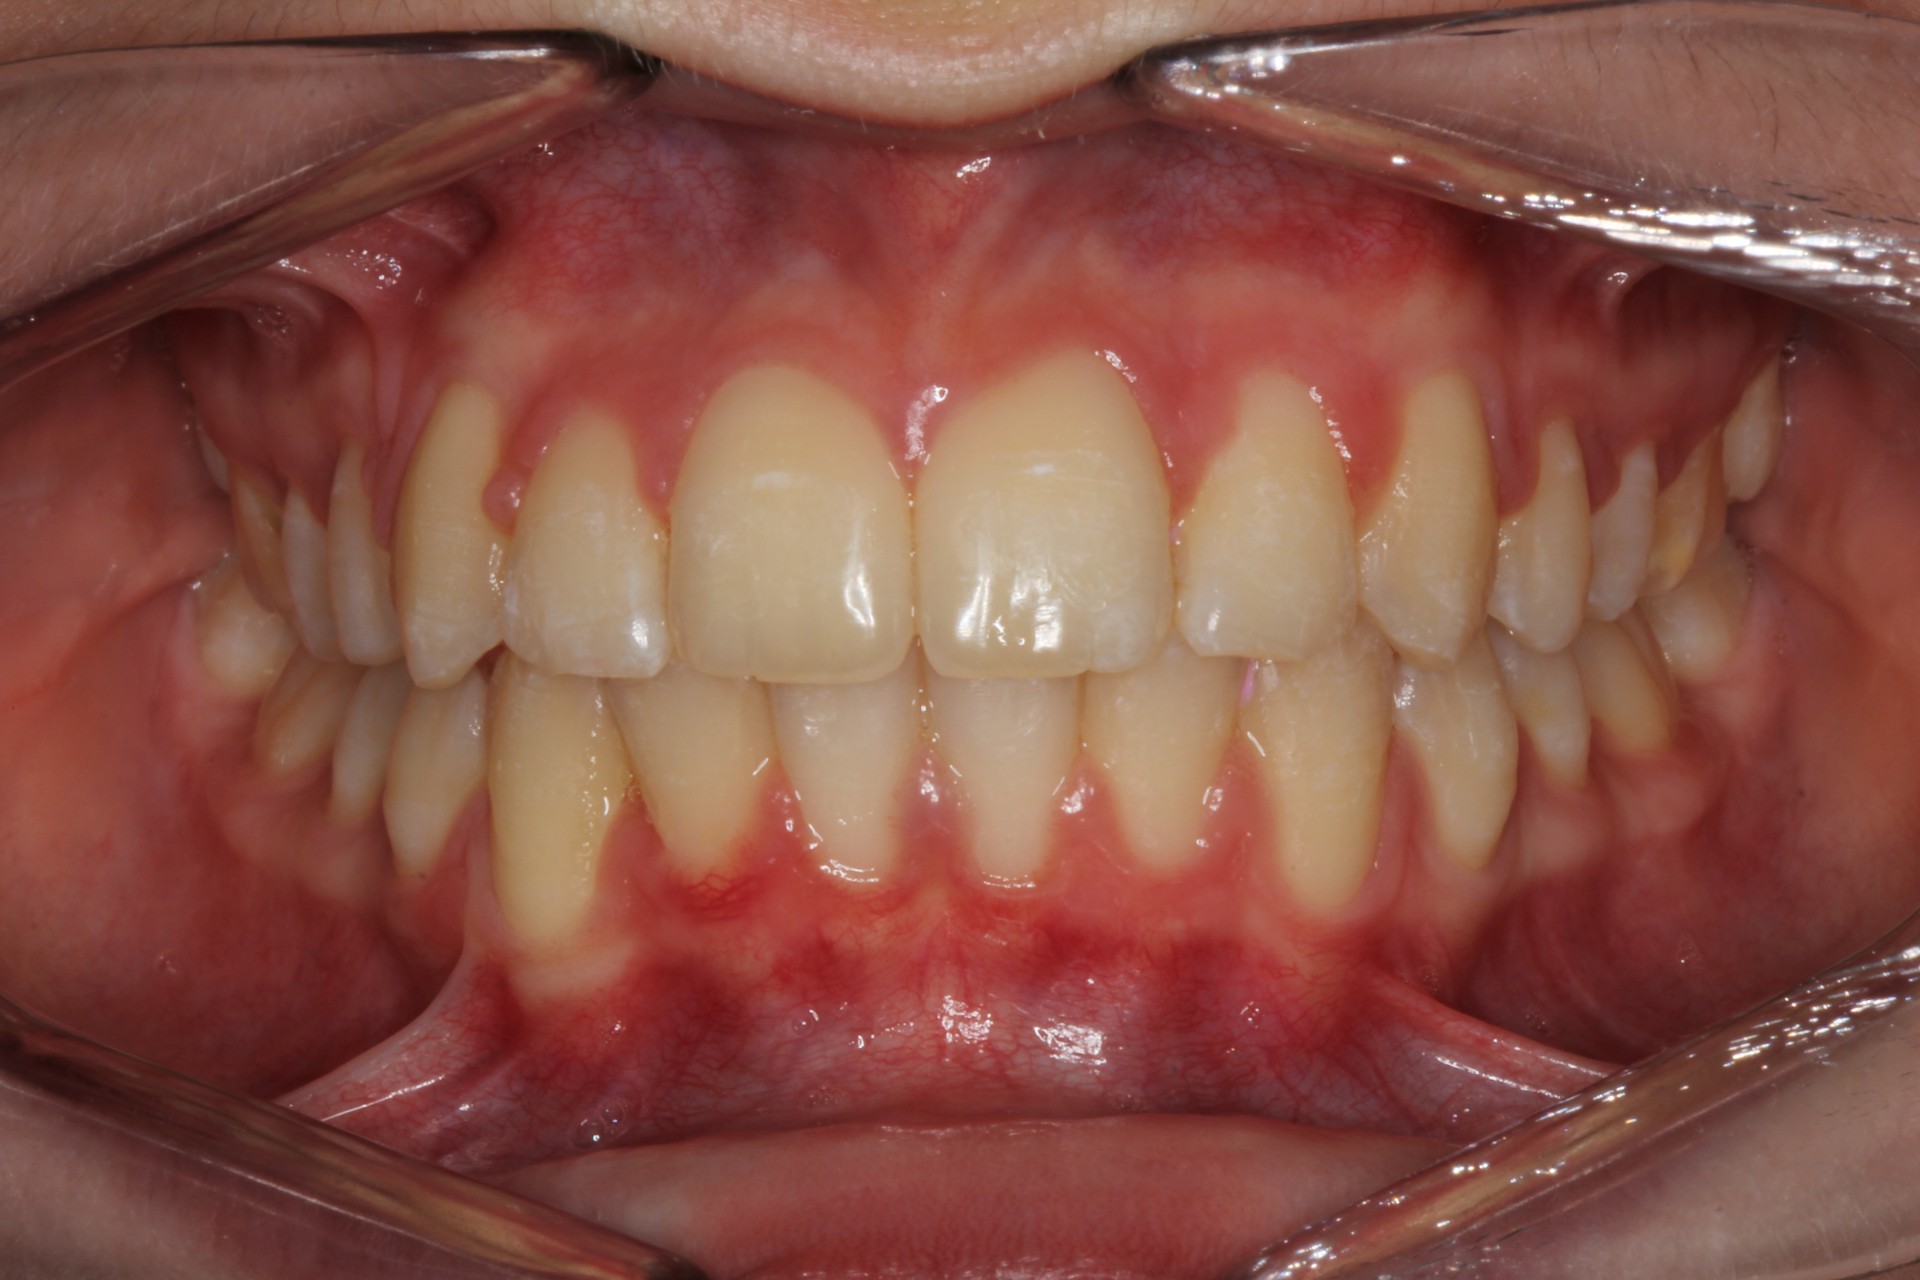

Protruding front teeth and spacing – Child case